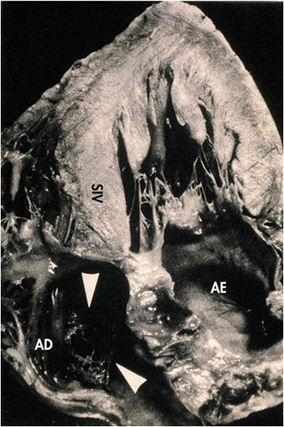

Seção transversa do Coração

Destaque para a massa muscular VE

(Imagem de cabeça para baixo)

AD = Átrio direito

AE = Átrio esquerdo

SIV = Septo intra ventricular

VE = Ventrículo esquerdo